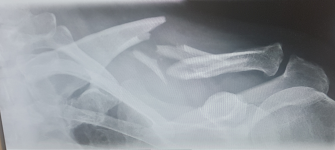

När bör nyckelbensfrakturer opereras?

* Vid hudhot eller hudpenetration.

* Vid tvärställt intermediärfragment.

* Vid kraftig förkortning (>2 cm).

* Vid mycket laterala frakturer.